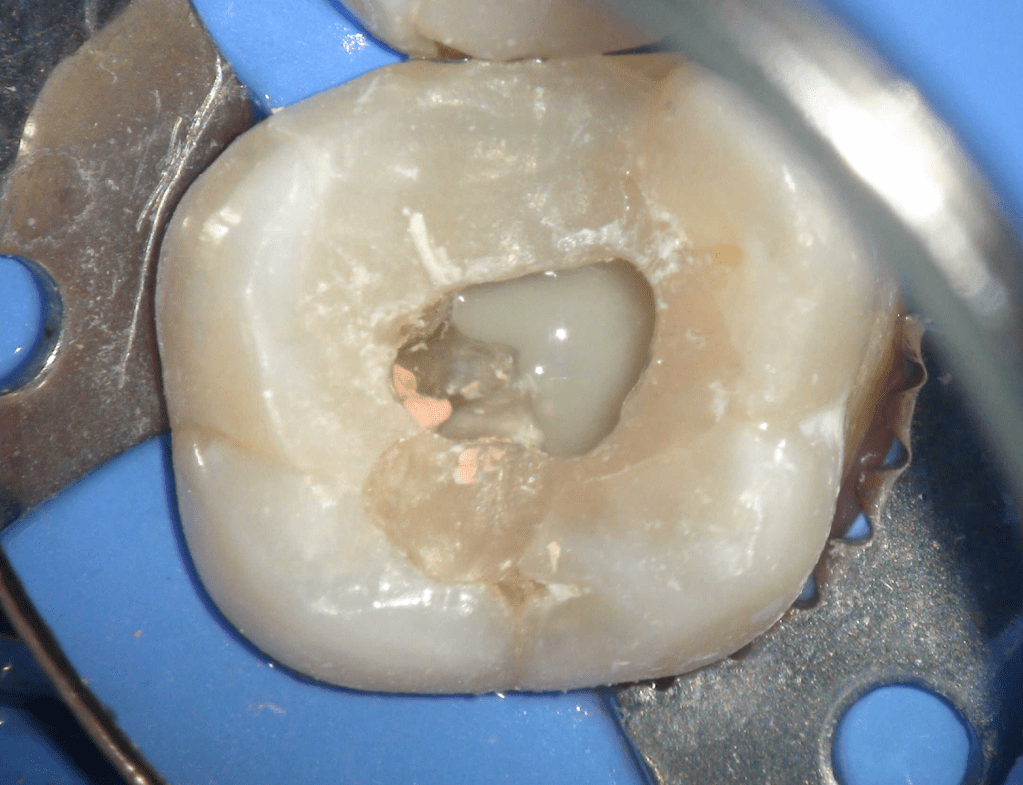

Acceso ultraconservador a través de incrustación reciente